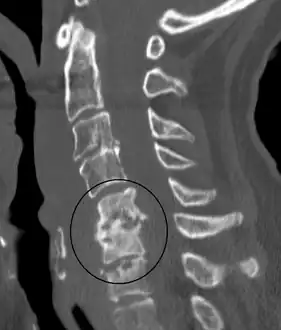

An infected disc at the level of C5 C6 causing neurological symptoms